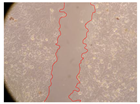

In the present study, the healing potential of 8 decoctions used in the preparation of ayahuasca was evaluated, using the wound scratch test. The evolution of the scratch created was monitored using microscopic images (Table 2) and the distance between the margins of the lesion was calculated (Table 3). Analysing the images that showed the evolution of the distance between the margins of the lesion and comparing them with the control samples, it was possible to verify that, in general, all the samples showed a great decrease in the lesion, and after 24 h of incubation, the samples of M. hostilis + P. harmala at 500 mg/L and P. viridis + B. caapi at 250 mg/L showed the best results. However, analysing the evolution of the distance calculated, only the sample of the commercial mixture at 250 mg/L after 2 h of incubation did not show a significant decrease. All other samples at different evaluation times, as well as the commercial mixture at 250 mg/L at the other times (8 h, 12 h and 24 h) showed a significant decrease in lesion margins compared to the control.

Table 2.

Microscopic images obtained from the scratch wound-healing assay with the samples of ayahuasca (magnification: 100×). The margins of the scratch appear in red.

These results are indicative of the healing activity of the samples tested. It is possible to observe in the images of Table 2 the migration of the fibroblasts incubated with the samples at different concentrations. In these images, it was possible to verify that the lesions closed over time, which was in accordance with the distance calculated between the margins of the lesion. As far as we know, to date there are no studies where the healing potential of ayahuasca has been evaluated, and it is not possible to compare the results now obtained. However, these results can be explained by the antioxidant and anti-inflammatory activity previously studied in these samples [], since it is reported that antioxidant activity and healing properties coexist in plant extracts []. Wound healing consists of the reconstruction of the lesion, involving several interactions between epithelial cells, growth factors, cytokines and chemokines. It has been reported that natural products, namely plant extracts, are involved in the proliferation of fibroblasts and keratinocytes, and may contain cell adhesion molecules, growth factors and cell signalling molecules, which can promote lesion reconstruction []. This in vitro assay, which, unlike conventional assays used to determine the healing properties of plant material, was non-invasive, allowed the screening of several samples with antibacterial, anti-inflammatory and antioxidant properties, which are important in wound healing [,].